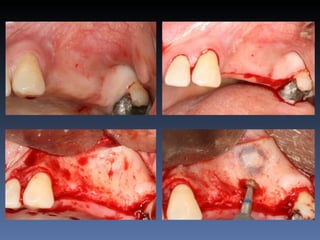

Maurício Zanetti

Data- 25-04-2012

Diagnóstico: Desdentado parcial

pré-maxila.

Plano de tratamento: Reabilitação pré-maxila com

instalação de 2 implantes endo-ósseos (1.1,.2.2), para

reabilitação protética fixa.